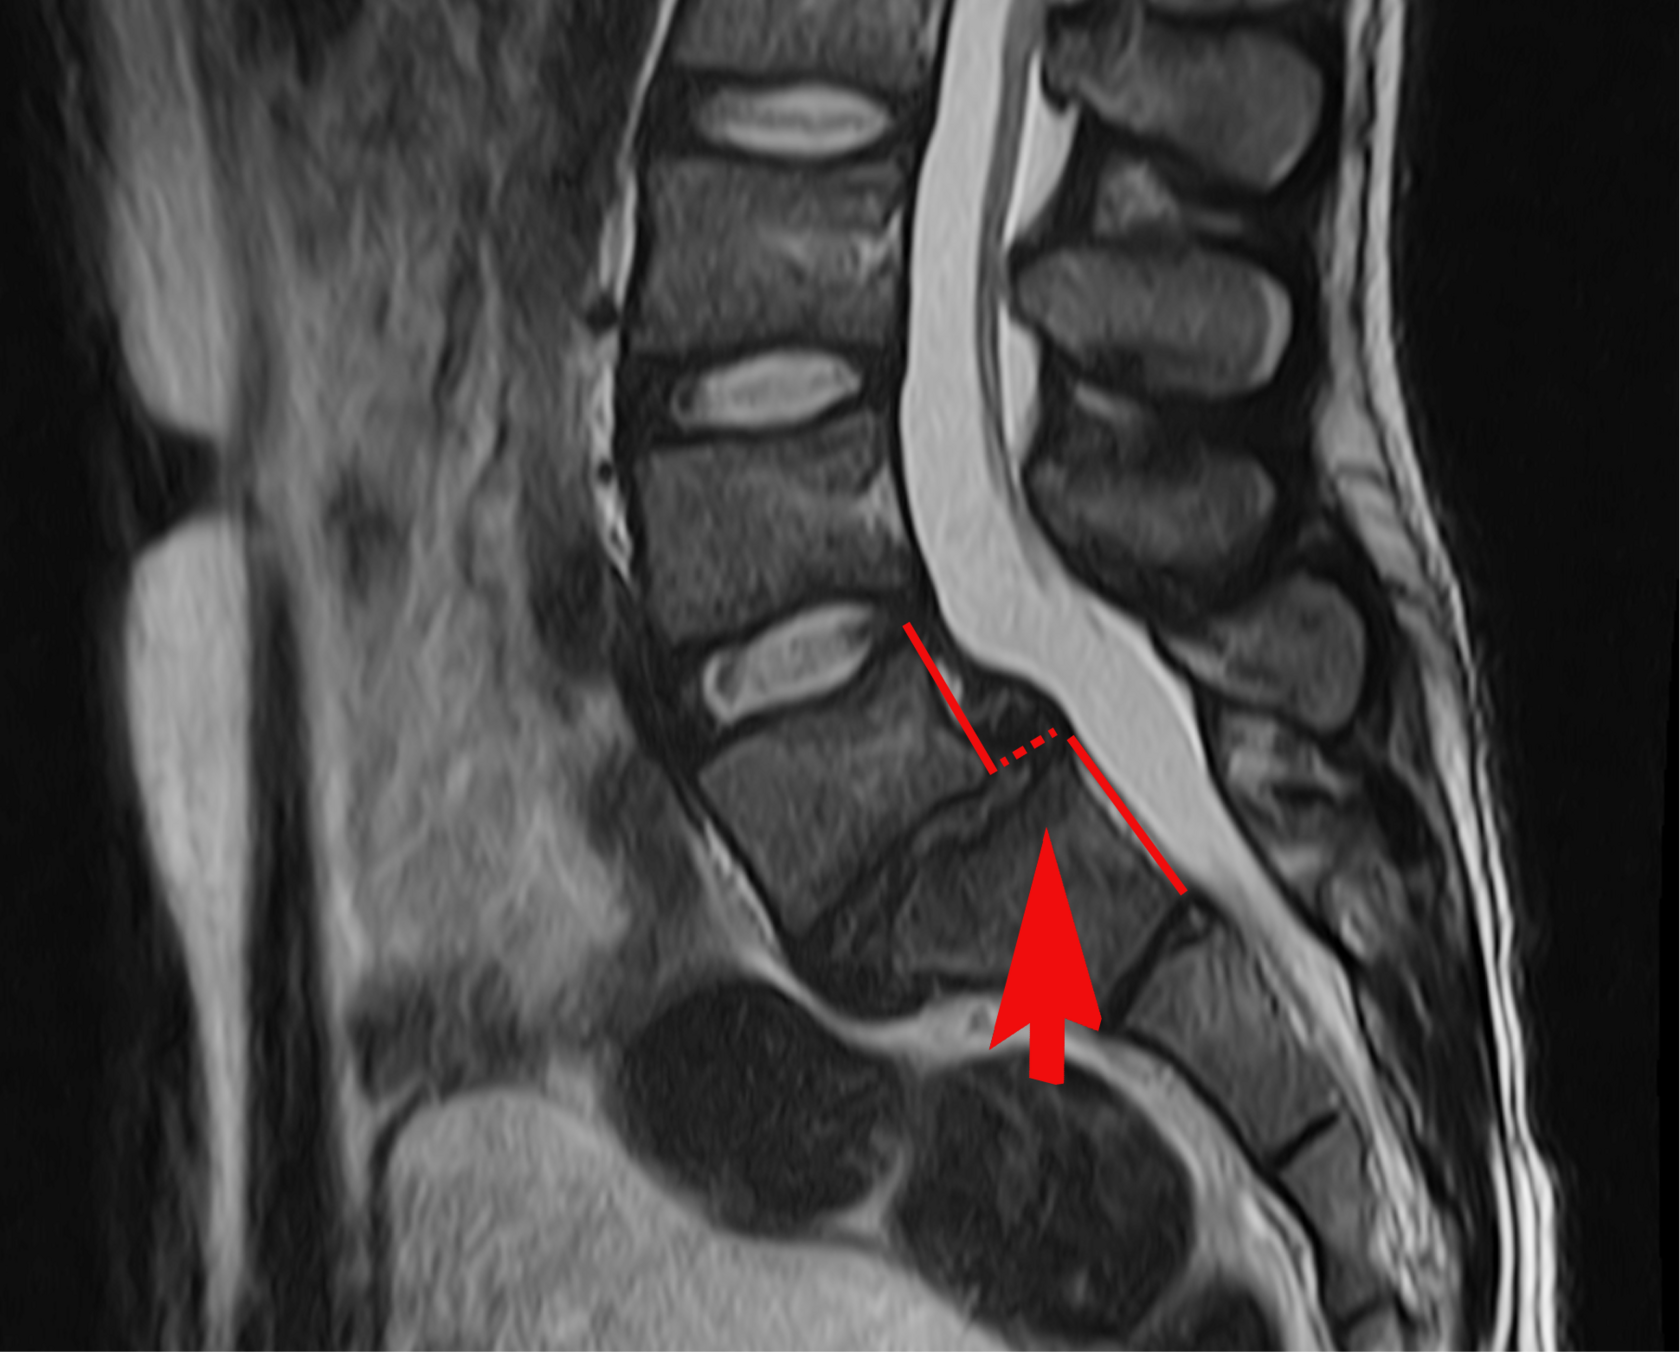

- смещение пятого поясничного позвонка (L5) вперёд на 7,6 мм — это значительное смещение, которое может вызывать сильную боль и нагрузку на нервные корешки;

- грыжа в этом же сегменте;

- несращение дужек L5 — анатомическая особенность, которая делает позвоночник менее стабильным и требует осторожного подхода.